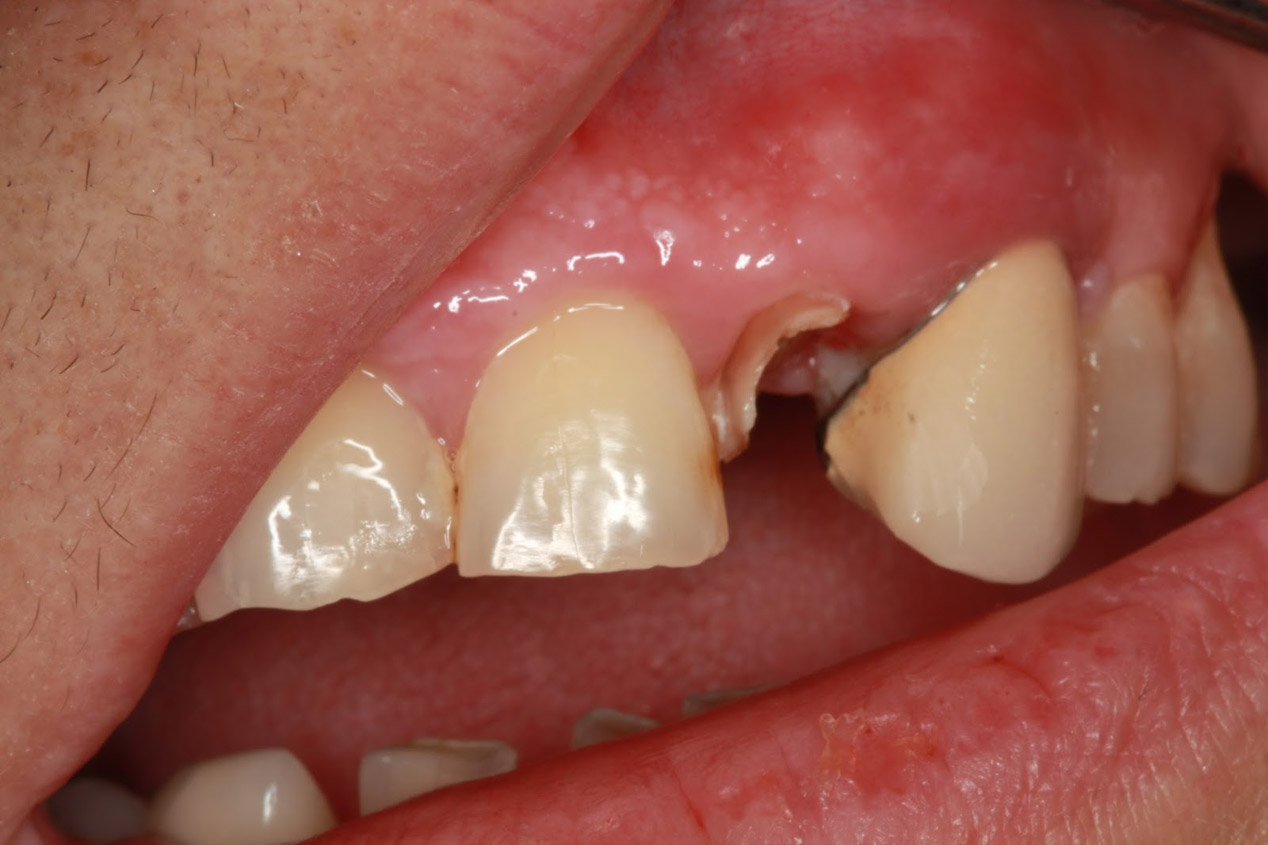

Χειρουργική αφαίρεση υπολειμμάτων ριζών

Κατά τη διάρκεια μίας εξαγωγής υπάρχει περίπτωση να σπάσει ένα κομμάτι της ρίζας του δοντιού μέσα στο φατνίο. Προκειμένου να αφαιρεθεί αυτό το υπόλειμμα, άλλοτε αρκεί μία αντιμετώπιση με απλούς χειρισμούς και άλλοτε χρειάζεται η συνδρομή της χειρουργικής. Η χειρουργική επίσης συμβάλλει στην ταχεία απομάκρυνση υπολειμμάτων ριζών σε περίπτωση όπου ένα δόντι έχει τερηδονιστεί σε τέτοιο βαθμό με αποτέλεσμα να έχουν απομείνει μόνο οι κατεστραμμένες ρίζες.